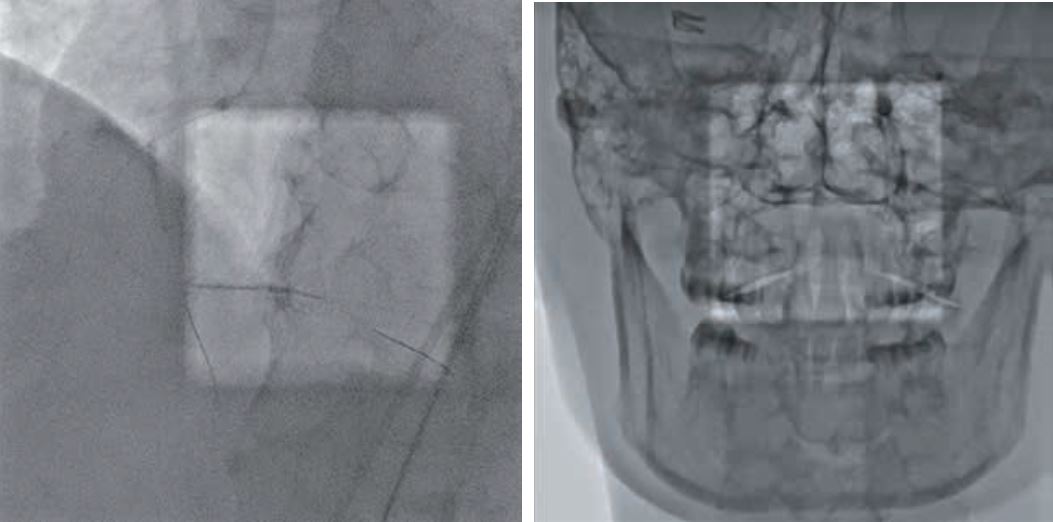

· Режим Spot Fluoro передбачає асиметричну, сфокусовану на проблемній ділянці колімацію з одночасним відображенням оточуючої області та збереженням дози до 70%.

- Режим SPOT ROI допомагає зменшити дозу поза межами області інтересу, одночасно дозволяючи візуалізувати навколишню анатомію завдяки застосуванню спеціального фільтру. Відображення не лише пристрою, а й навколишньої анатомії під час встановленняпристрою є дуже важливим для успішного результату.

- Dose Tracking System (DTS) – Система стеження за дозою обраховує та відображає в реальному часі дозу на шкіру, отриману пацієнтом. У разі досягнення попередньо заданого критичного рівня дози така система попередження допомагає лікарям уникнути ризику променевого ураження шкіри за рахунок зміни проекції, SID, частоти кадрів.